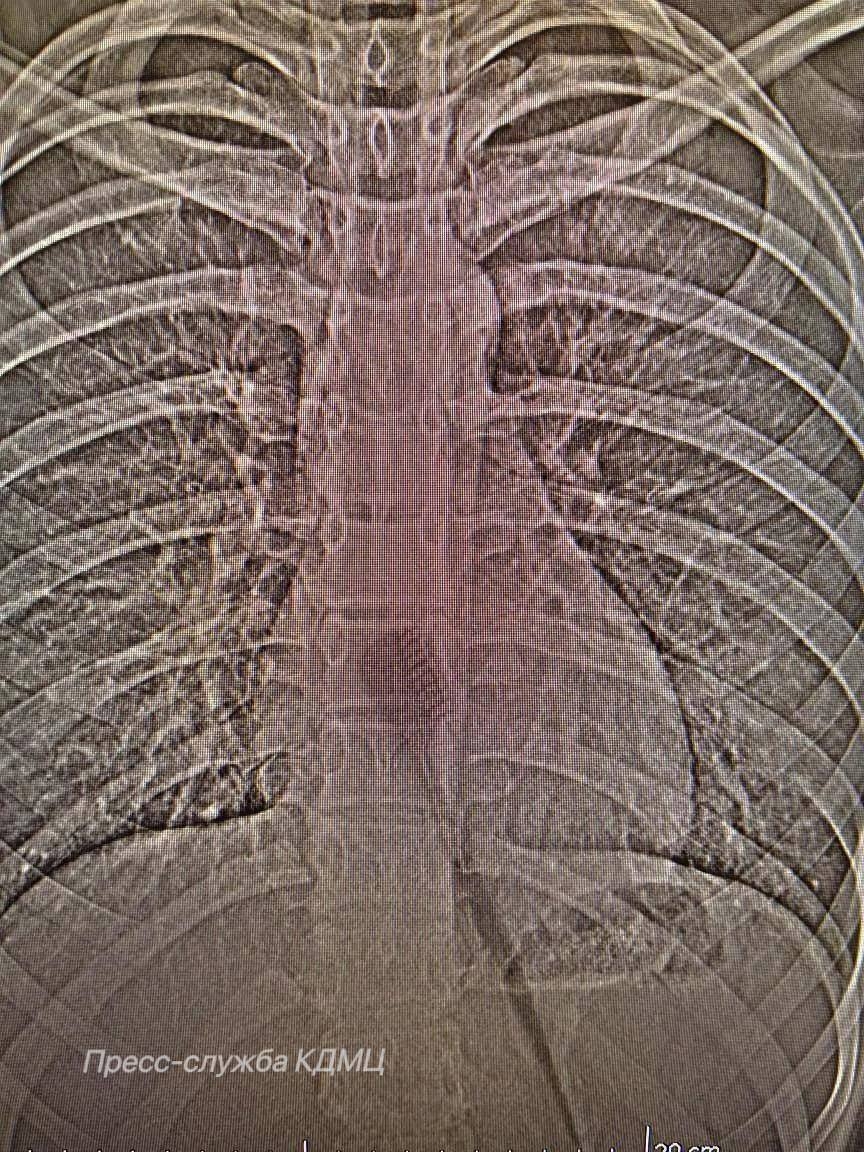

Школьница проглотила зубную щетку во время утренней гигиены. На момент поступления ребенка в медучреждение предмет находился в желудке и частично в пищеводе, создавая риск повреждения этих органов.

Девочке провели эндоскопическую операцию – малоинвазивный метод, позволяющий извлечь инородное тело без полостного вмешательства. Это позволило хирургам аккуратно удалить предмет через естественные пути, минимизируя риск осложнений и ускоряя процесс восстановления юной пациентки. В итоге школьница, успешно пройдя период реабилитации, была выписана из КДМЦ.